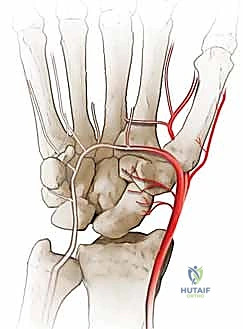

المشكلة الكبرى التي تواجه العظم الزورقي تكمن في التروية الدموية (Blood Supply). الدم يدخل إلى العظم الزورقي من الجزء البعيد (Distal pole) ويتجه نحو الجزء القريب (Proximal pole) في اتجاه عكسي (Retrograde). لذلك، عند حدوث كسر في منتصف العظم، ينقطع الدم عن الجزء القريب، مما يؤدي إلى عدم التئام الكسر (Nonunion) وفي كثير من الأحيان موت العظم (Avascular Necrosis).

تُعد عملية استئصال القطب البعيد للعظم الزورقي (Excision of the Distal Pole of the Scaphoid) حلاً جراحياً ذكياً ومبتكراً. الفكرة الميكانيكية وراء هذه الجراحة هي: "إذا كان القطب البعيد للعظم الزورقي هو الذي يحتك بعظم الكعبرة ويسبب الألم والخشونة، فلنقم بإزالته مع الحفاظ على باقي هياكل الرسغ".

- الشق الجراحي: يقوم الدكتور هطيف بعمل شق جراحي صغير ودقيق (حوالي 3-4 سم) في الجهة الظهرية أو الراحية للرسغ، مع مراعاة الحفاظ على الأعصاب الحسية والأوتار المحيطة.

- الوصول إلى العظم الزورقي: يتم فتح كبسولة المفصل بحذر شديد للوصول إلى العظم الزورقي التالف.

- الاستئصال الدقيق: باستخدام أدوات جراحية ميكروسكوبية دقيقة، يتم استئصال حوالي 3 إلى 4 مليمترات من القطب البعيد للعظم الزورقي. هذه الكمية كافية لمنع الاحتكاك مع عظم الكعبرة، وفي نفس الوقت تحافظ على استقرار الأربطة.